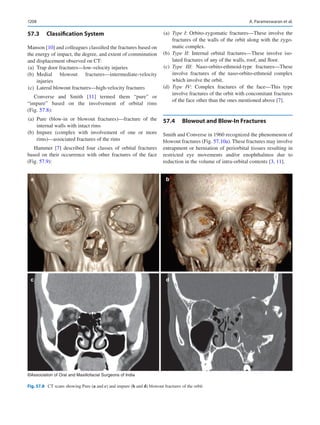

icine man for their healthcare. Direct to consumer marketing